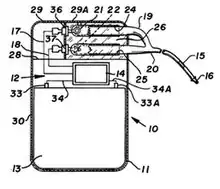

Appareil

Il est composé d’un boîtier et d’une ou plusieurs sondes. Des systèmes sans sondes ont été développés (capsules contenant l'électronique et la batterie et mis en place dans le ventricule droit[9])

Boitier

Il se compose :

- d’une source d’énergie (une batterie fonctionnant au Lithium-Ion). Elle n'est pas rechargeable (le boîtier en fin de vie doit être remplacé lors d'une opération chirurgicale). L'avantage de ce type de batterie est sa durée de fonctionnement prolongée, avec une baisse progressive de la tension qui permet d'estimer la durée de vie résiduelle[10] ;

- d’une électronique permettant de délivrer des impulsions électriques calibrées en fréquence, amplitude et largeur d’amplitude ;

- d’un système de détection de l’activité électrique spontanée du cœur, permettant de ne fonctionner qu’en cas de défaillance de celle-ci (mode sentinelle) ;

- d’un système de mesure permettant de connaître la résistance des sondes (impédance), la charge de la pile, les statistiques de fonctionnement ;

- d'une antenne radiofréquence permettant la communication de données à travers la peau vers un dispositif externe.

Suivant les modèles, le boîtier comporte également :

- d'un ou plusieurs capteurs d’activité du patient permettant de faire varier le rythme cardiaque suivant l'intensité de cette activité. La pile est alors dite « asservie à l’effort ». Le capteur le plus simple est un détecteur de mouvement inertiel qui postule que l’intensité de ce dernier est proportionnel à l’effort du patient. Cependant, des capteurs dits physiologiques ont été développés, comme la mesure de la ventilation ou du segment ST[11] ;

- des capteurs permettant l'évaluation de la fonction cardiaque. Une mesure de l'impédance entre la sonde et le boîtier est ainsi corrélé au contenu en eau de la cage thoracique et peut baisser en cas d'œdème pulmonaire[12], même si la sensibilité et la spécificité de ce genre de mesure n'est pas optimale[13] ;

- des algorithmes permettant le basculement d’un mode à l’autre en cas de troubles du rythme cardiaque, de réguler la tension de sortie suivant les situations, ce qui permet d’allonger la durée de vie de la pile ;

- un système d'exportation des données par téléphonie permettant d'avertir le centre implanteur d'éventuels problèmes sans que le patient ait besoin de se déplacer (télémédecine).

La taille du stimulateur a aussi été considérablement réduite et reste principalement limitée par celle de la batterie/pile intégrée (jusqu'à 10 centimètres cubes).

Sondes

Souples, elles relient le boîtier au cœur. Elles sont constituées d'une âme conductrice et d'une gaine isolante. Elles peuvent être unipolaires (une seule électrode distale) ou bipolaires (deux électrodes distales). Afin d'assurer un meilleur contact avec le muscle cardiaque, elles peuvent être pourvues d'une tête relarguant un médicament luttant contre l'inflammation locale. La fixation des sondes au niveau du muscle cardiaque peut être faite de manière passive (« à barbe » sous forme d'aspérités) ou active (« à vis »). La sonde peut être rigidifiée transitoirement, ce qui facilite la mise en place, en y introduisant un fin guide métallique, retiré en fin de procédure[14]. Elles étaient en Elgiloy, alliage de cobalt, de chrome et de nickel durant les années 1970. Elles sont depuis dans des alliages comprenant titane, iridium et carbone.

Un boîtier peut être connecté à une seule sonde (pile monochambre ou monofocale) ou à deux sondes (pile double chambre ou bifocale). Dans ce dernier cas, l'extrémité de la première sonde est positionnée dans l'oreillette droite, celle de la seconde dans le ventricule droit.

Dans certains cas, il existe une troisième sonde dont l'extrémité est située dans le sinus coronaire en contact du ventricule gauche. Il s'agit alors d'un stimulateur triple chambre (ou biventriculaire), employé dans le traitement de certains types d'insuffisance cardiaque. Des systèmes quadri-chambres ont aussi été développés et implantés. Ils restent cependant d'utilisation rare.